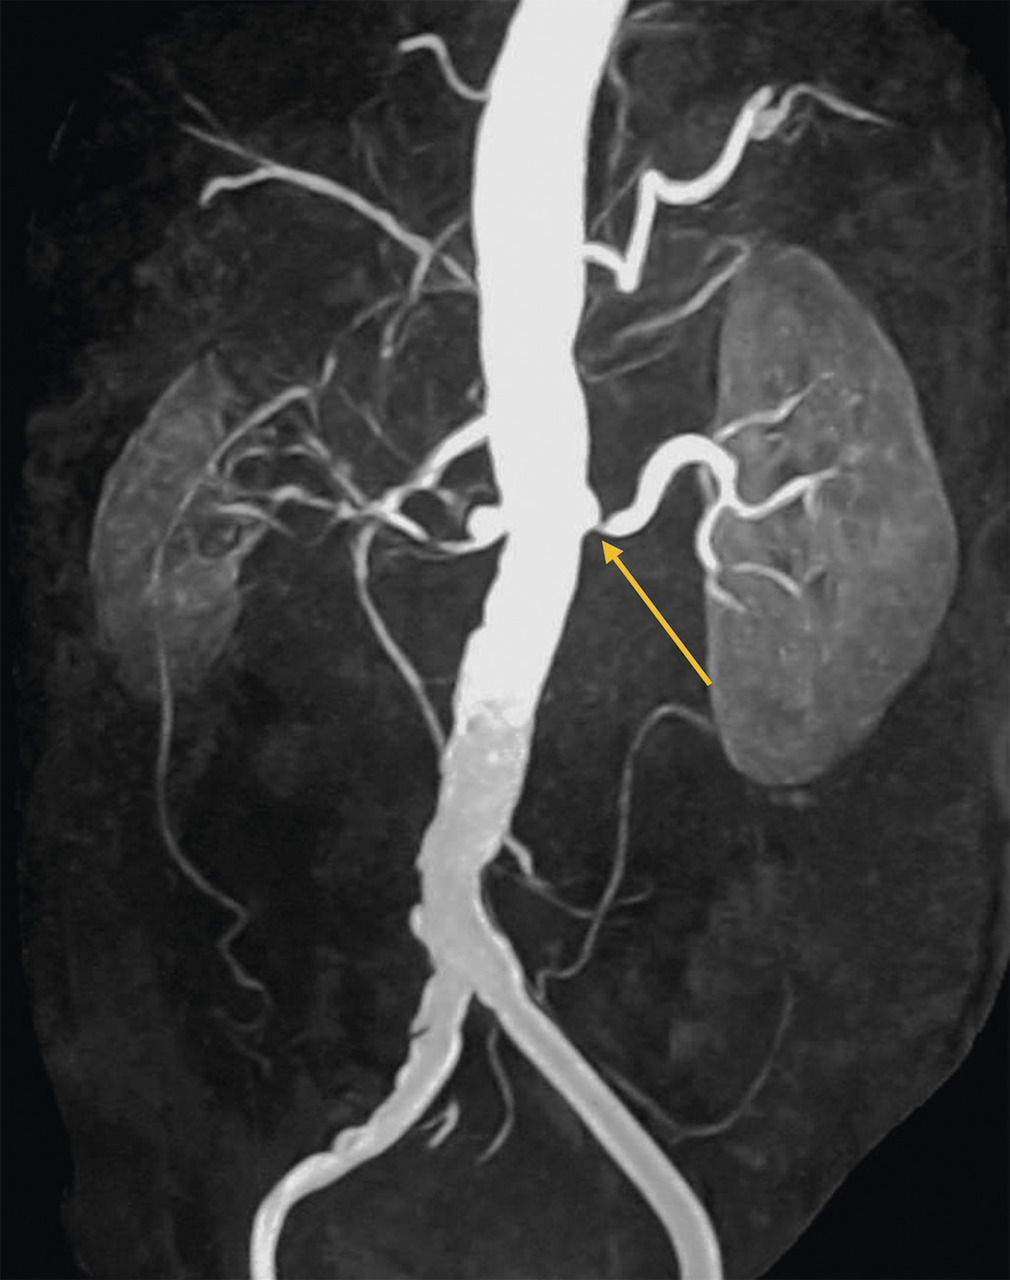

L’échographie-Doppler, l’angio-tomodensitométrie (angio-TDM [fig. 2] et l’angio-imagerie par résonance magnétique (angio-IRM) [fig. 3] permettent le diagnostic de sténose de l'artère rénale. Ils estiment à la fois le degré de sténose (exprimé en pourcentage de réduction du diamètre) et l’impact sur la vascularisation d’aval. Ces 3 examens sont validés et recommandés en première intention. Leur utilisation dépend de l’accessibilité et des habitudes locales. Il est à noter que l’écho-Doppler, très sensible et spécifique dans la sténose de l'artère rénale athéromateuse sous réserve d’un opérateur entraîné, est de sensibilité imparfaite dans la fibrodysplasie, dans laquelle l’angio-TDM est l’examen de référence.

Dans la sténose de l'artère rénale athéromateuse, on retrouve une plaque habituellement unique, plus une moins calcifiée, ostiale, proximale ou tronculaire, responsable d’une réduction du diamètre endoluminal d’une ou des artères rénales (fig. 2 et 3).